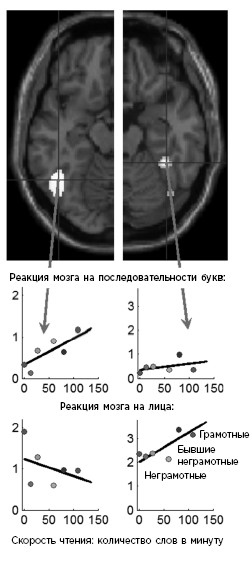

Данный парадоксальный прогноз мои коллеги и я проверили экспериментально. Чтобы составить подробную карту областей, меняющихся под влиянием грамотности, мы просканировали мозг неграмотных взрослых в Португалии и Бразилии, а затем сравнили эти данные с результатами обследования жителей тех же деревень, которым посчастливилось научиться читать в школе (в детском или уже во взрослом возрасте)190. Как и следовало ожидать, с приобретением навыков чтения многие области стали восприимчивы к печатному слову (см. цветную иллюстрацию 14). Покажите предложение, слово за словом, неграмотному человеку, и вы обнаружите, что его мозг реагирует очень слабо: активность охватывает первичные зрительные области, но дальше не распространяется, поскольку буквы не могут быть распознаны. Теперь покажите ту же последовательность слов взрослому человеку, который умеет читать. Вы обнаружите, что на нее откликнется гораздо более обширная сеть корковых нейронов, в том числе область для букв в левой затылочно-височной коре, а также все классические речевые центры, связанные с пониманием языка. Усиленная активность наблюдается и в первичных зрительных областях: с приобретением навыка чтения они, по всей вероятности, подстраиваются под распознавание мелкого шрифта191. Чем быстрее человек читает, тем активнее эти области реагируют на печатные слова и тем сильнее становятся связи между ними: по мере автоматизации навыка чтения преобразование букв в звуки заметно ускоряется.

Противоположный вопрос звучит так: существуют ли области, активность которых не увеличивается, а, наоборот, уменьшается? Ответ – да: у неграмотных людей мозг интенсивнее реагирует на лица. Чем лучше мы умеем читать, тем слабее соответствующая активность в левом полушарии, особенно в том месте, где письменные слова находят свою нишу – в области зрительной формы слова. Мозг как будто «насильно» освобождает место для букв, в результате чего чтение начинает препятствовать выполнению изначальной функции – распознаванию лиц и объектов. Разумеется, все, кто умеет читать, вовсе не разучиваются распознавать лица, а значит, эта функция не просто вытесняется из коры. Как показывают данные, при овладении чтением реакция на лица ослабевает в левом полушарии, которое у большинства людей специализируется на речи, и одновременно усиливается в правом192.

Согласно гипотезе нейронного рециклинга, научение чтению конкурирует с изначальными функциями зрительной коры, в данном случае – с распознаванием лиц. С повышением уровня грамотности – от абсолютной неграмотности до беглого чтения – в левом полушарии усиливается реакция на написанные слова, а функция распознавания лиц смещается в правое полушарие.